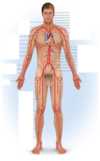

Identify the arteries

Identify the veins

Brachiocephalic trunk

Superior mesenteric artery